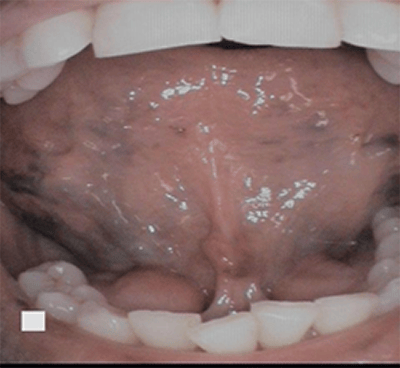

Caviar tongue is a condition recognized by purplish veins located on the ventral side of the tongue. Veins are normally visible underneath (ventrally) the tongue since the mucous membrane is so thin and translucent. However, with caviar tongue, the blood vessels become dilated and tortuous and appear round and black (resembling caviar).1

Caviar tongue is also referred to as sublingual varices (plural) and varix (singular) and look like varicose veins in the tongue (see Figure 1). It is a benign, asymptomatic, venous lesion.1

Caviar tongue occurs in a few different sites. It is commonly noticed under the tongue along the sublingual vein, the floor of the mouth at the opening of the sublingual glands, and along the lateral, ventral (underside) of the tongue. It’s rarely seen on the lips and buccal mucosa.

It originates as small outpouching of the veins and gradually elevates the overlying thin mucosa varying from red to purple, resembling buckshot (see Figure 2) or caviar with an iridescent surface.1 They originate bilaterally from the posterior of the tongue and end at the apex of the tongue.2 Histologically, a sublingual varix is a dilated vein with no inflammatory changes. The endothelium is hypoplastic, and the wall is thick and cellular.